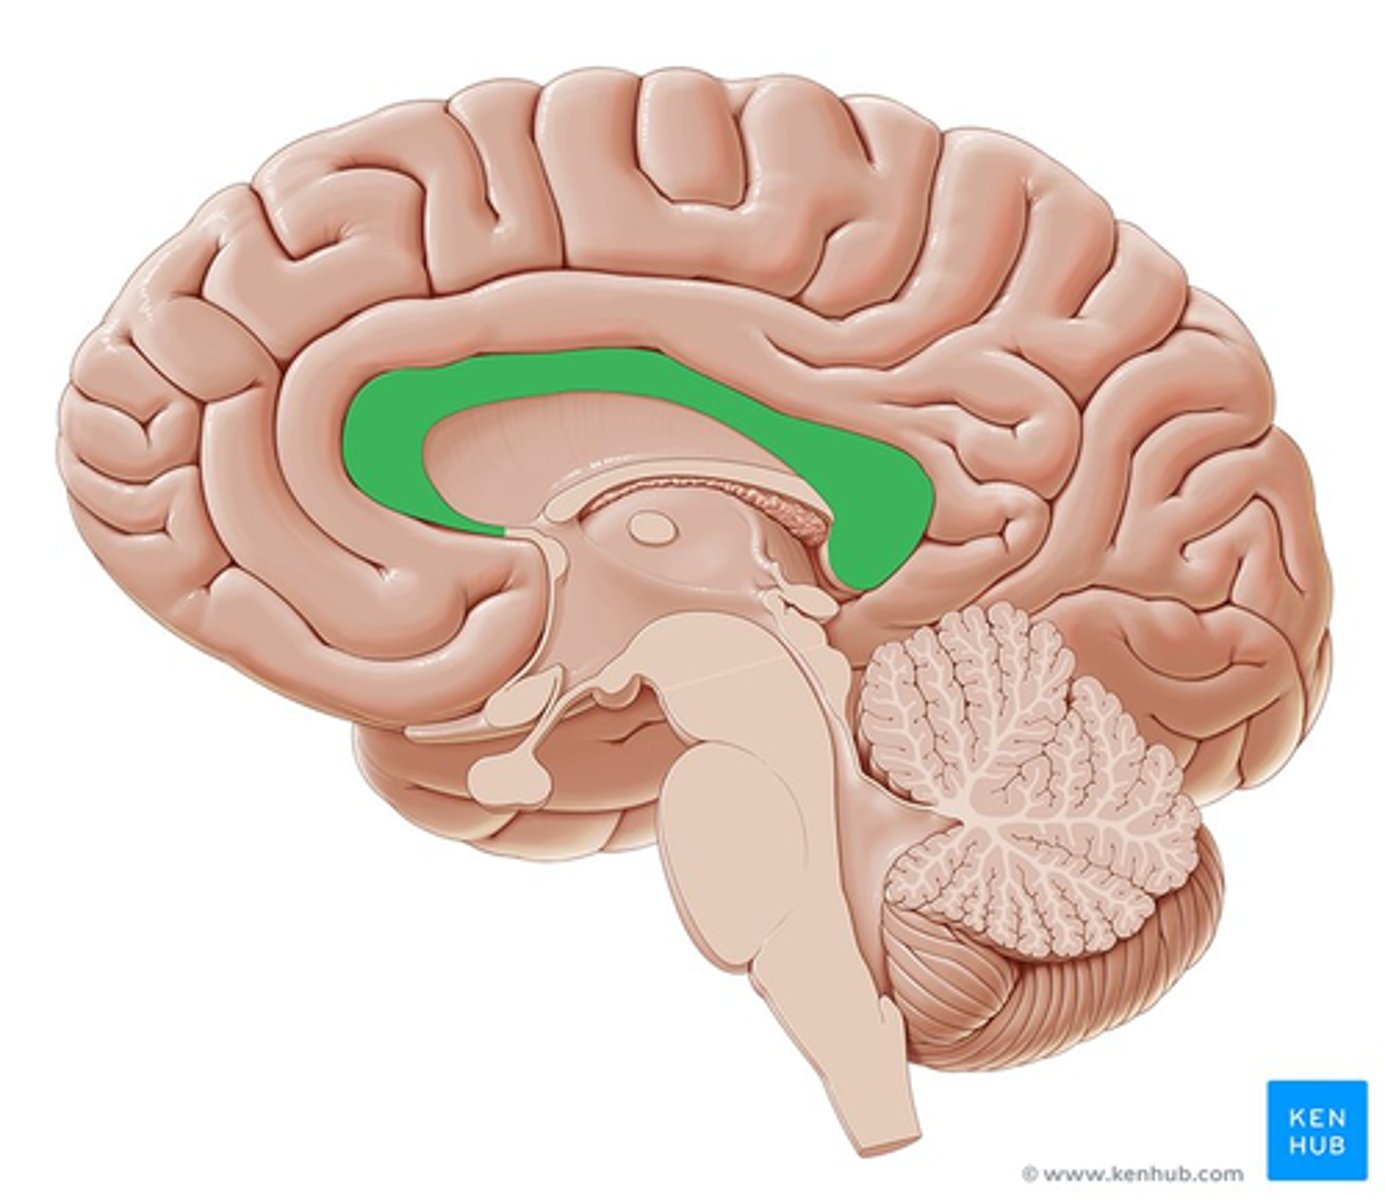

lateral ventricle